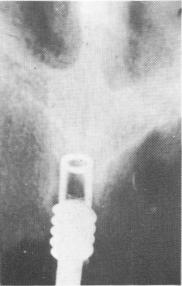

A hollow threaded vent-plant was screwed into the nasal septum (Fig. 10-265). Care was taken to angle

Fig. 10-265. An internally threaded vent-plant was screwed into the center of the anterior maxillary process.

2 Internally threaded ventplant screwed into maxillary process